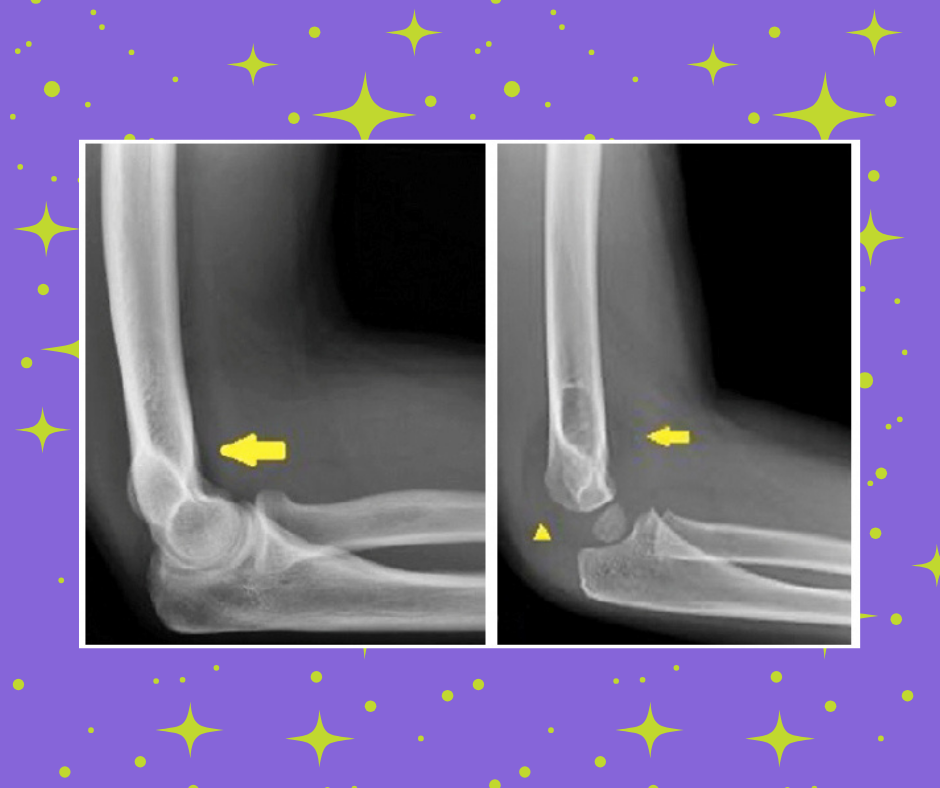

How to Approach the Pediatric Elbow

Here it is: the dreaded pediatric elbow. Is it a fracture? An ossification center? Shouldn't there be a bone there? By using a systematic approach to reading elbow x-rays, you can begin to feel more confident and adept at evaluating the subtle signs of pediatric fractures.